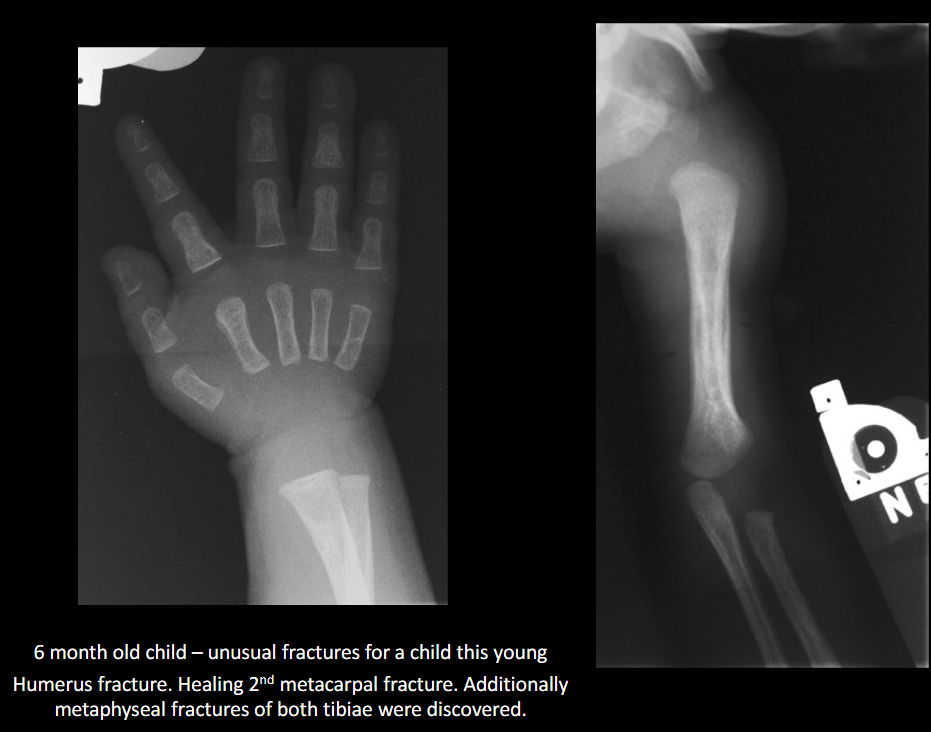

Define NAI.

Non-accidental injury/trauma; deliberate physical harm to a child.

Classic metaphyseal injury in NAI?

Corner/bucket-handle fracture.

Why are posterior rib fractures suspicious for NAI?

From squeezing the thorax.

Preferred initial imaging in suspected NAI?

Skeletal survey (not a ‘babygram’).

Common intracranial finding in NAI on CT?

Subdural hematoma.